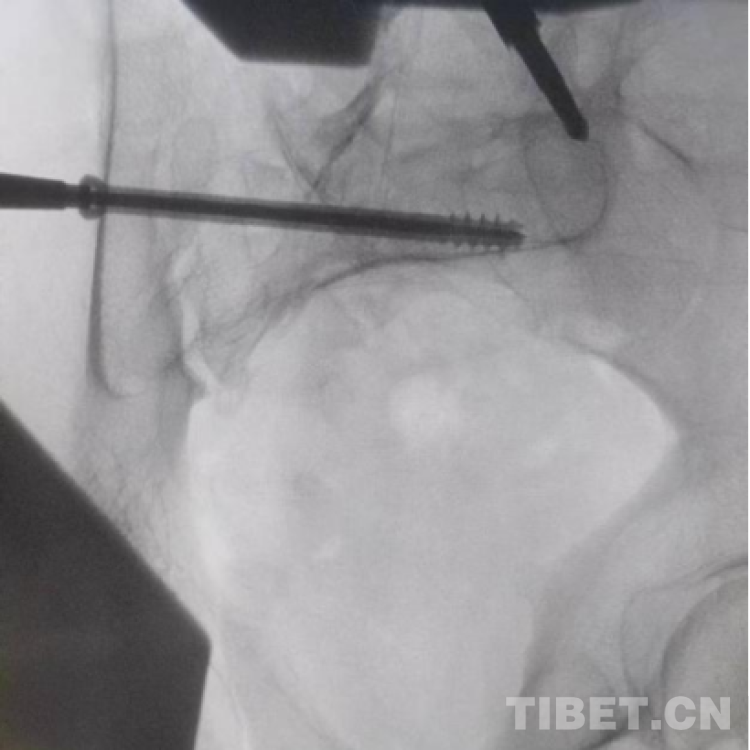

图为透视下见置入的骶髂螺钉,位置、长度精准,无丝毫偏差